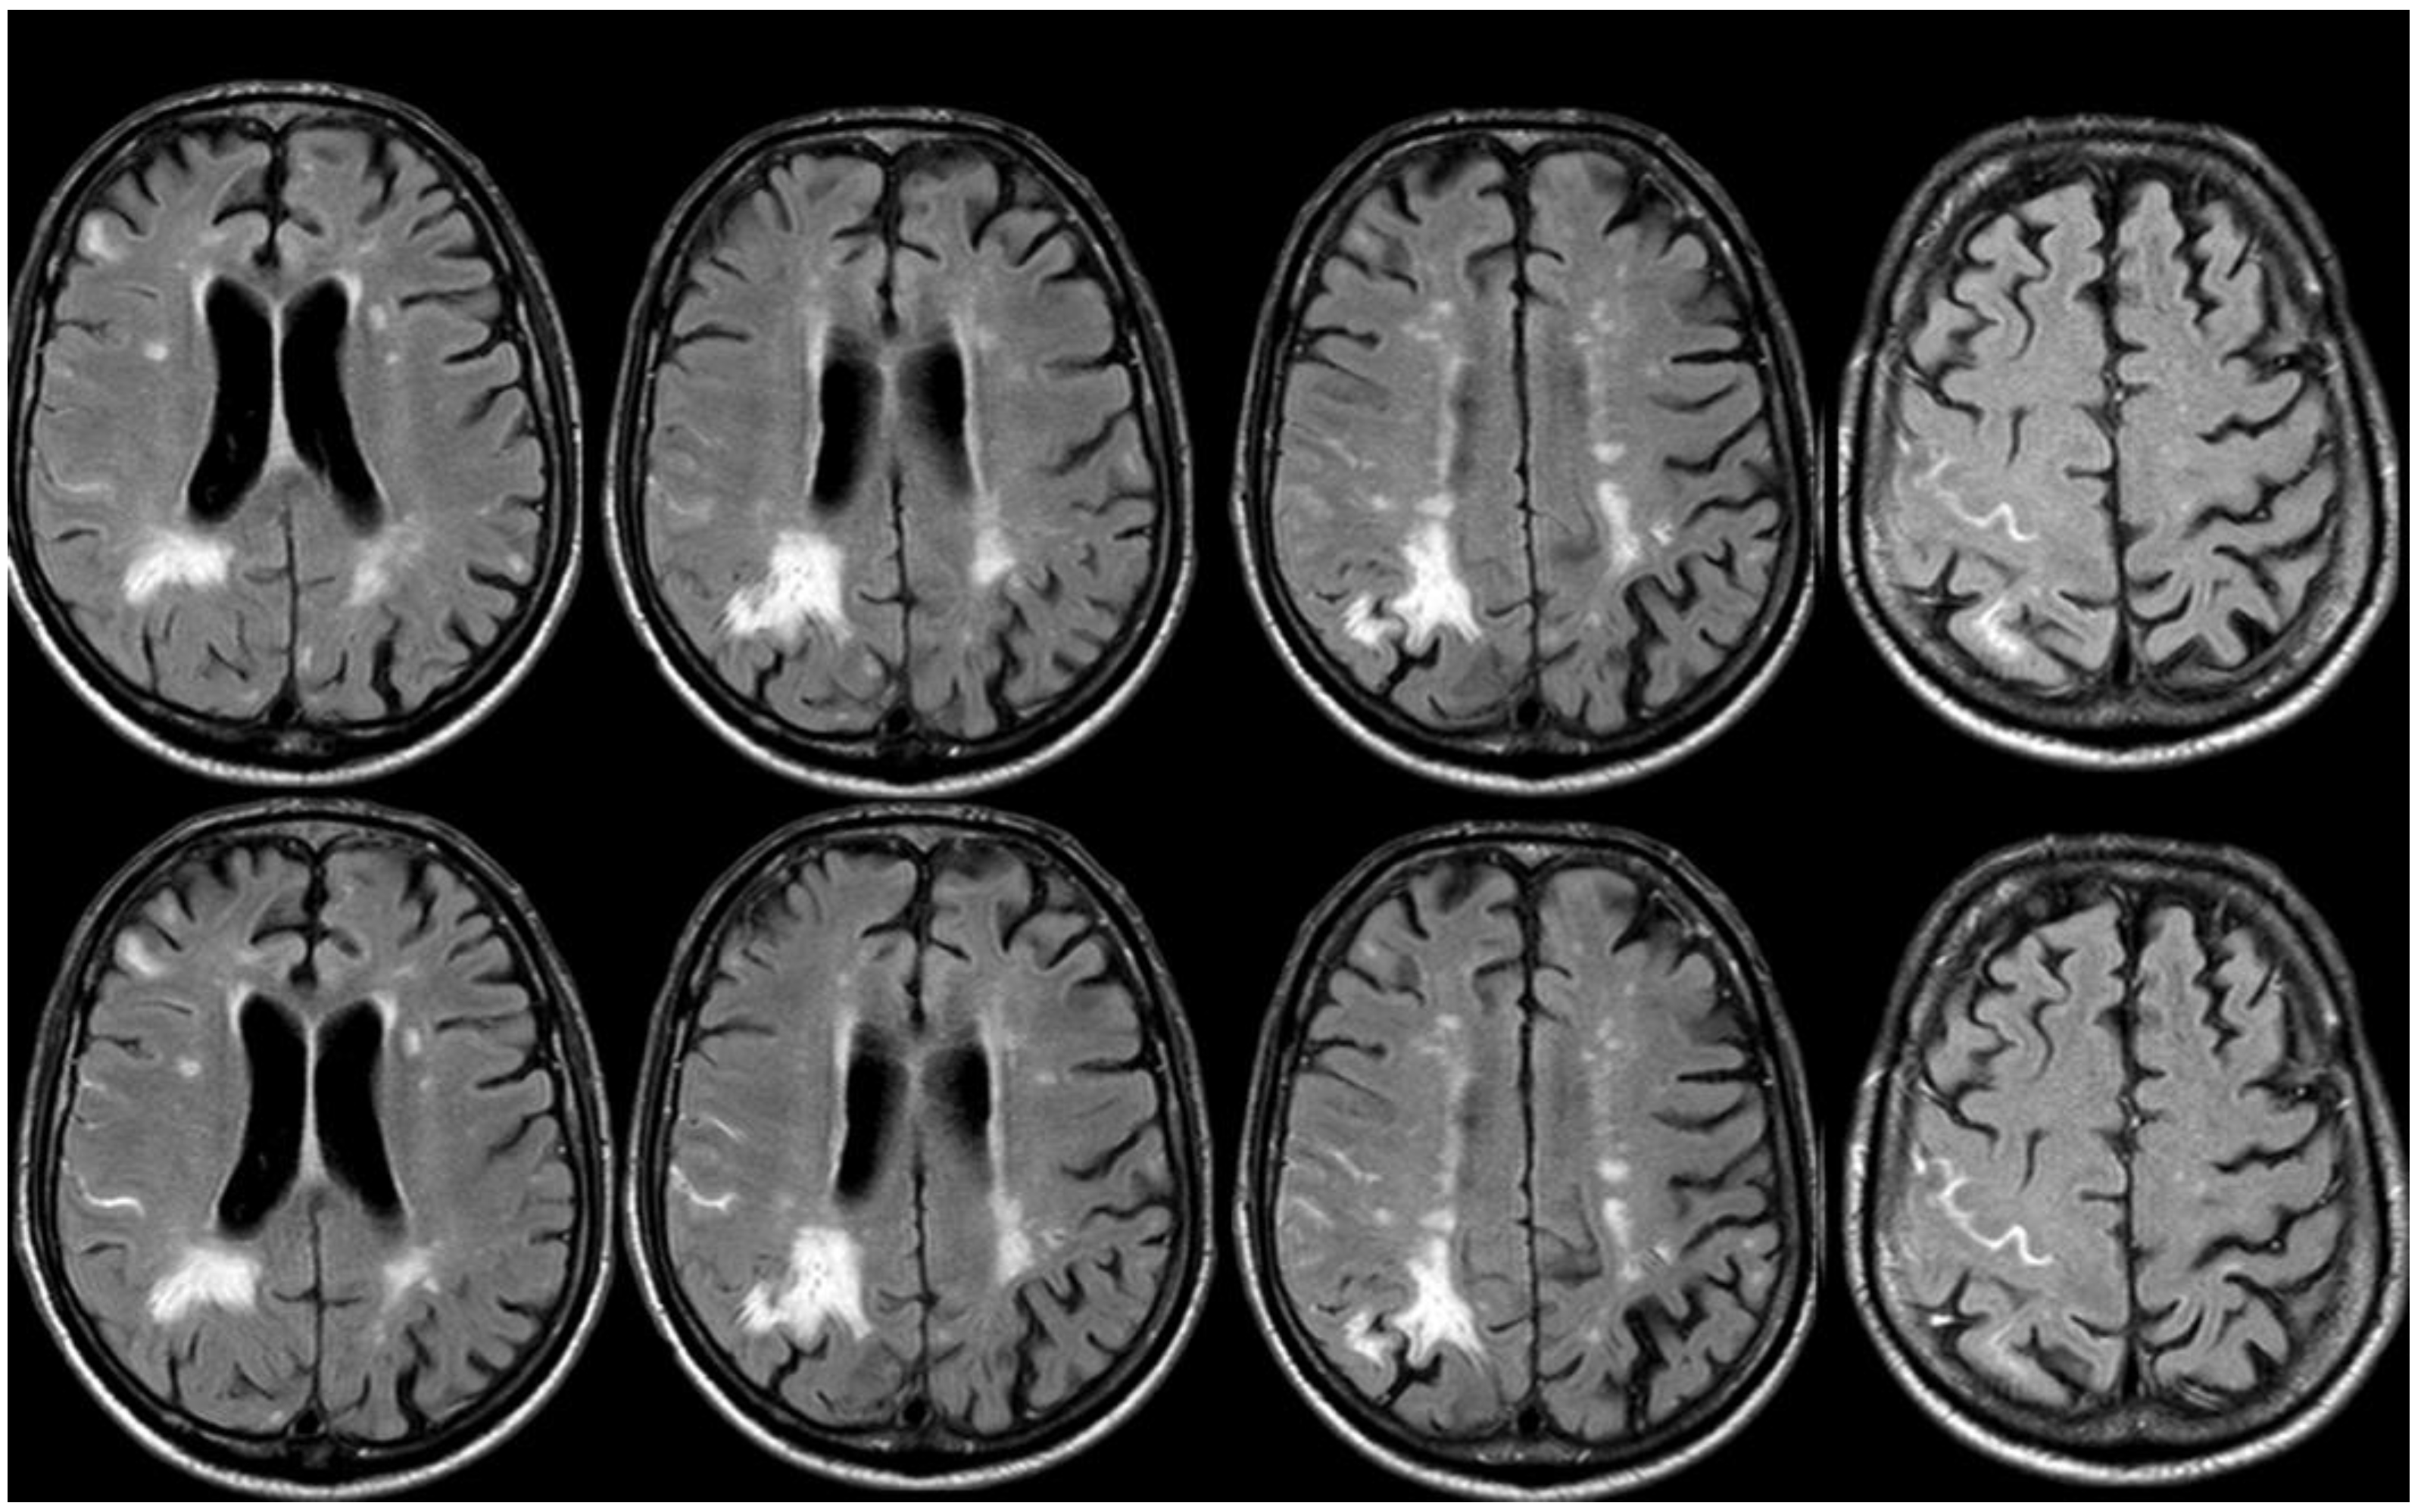

3. May 2014: CAA-Related Inflammation